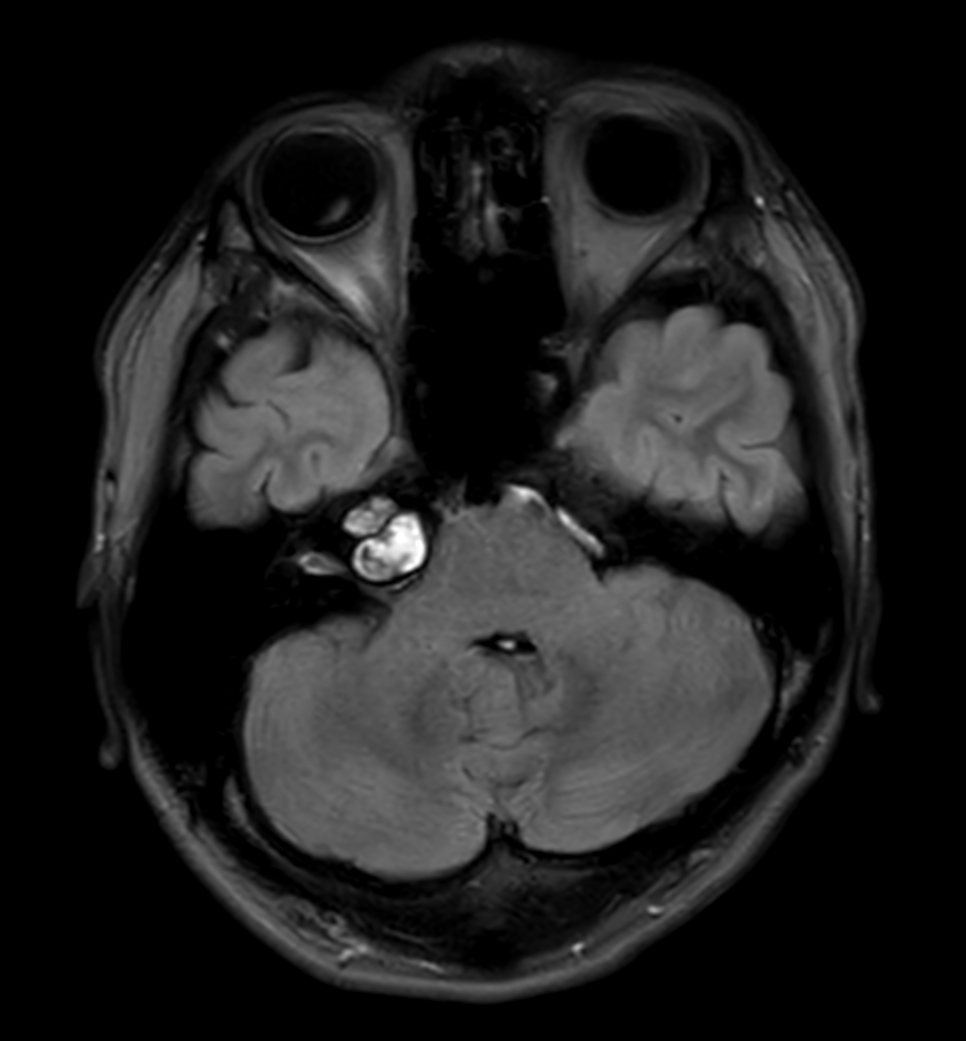

Patient with an IAC lesion. Comparing different DWI methods (EPI, TSE, ZOOM). Compressed SENSE is added to all TSE sequences to decrease scan times, thereby shortening the time the patient has to spent in the magnet. The dS Head 32ch coil is used to enhance image quality.

DWI TSE XD (b1000)

DWI TSE XD high res (b1000)